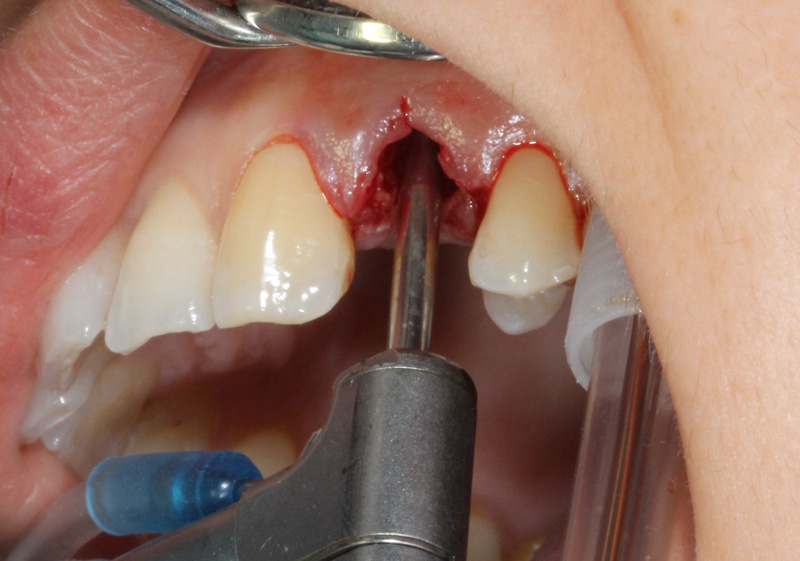

A distanza di qualche giorno viene esguita l'estrazione con l'aiuto di del Soniflex (Komet) con le rispettive punte al fine di non danneggiare l'osso corticale.

L'impianto inserito dopo l'estrazione è un Starumann Tapered Effect di 4,1 mm di diametro e 12 mm di lunghezza.

A causa di un gap marginale > di 2 mm viene ritenuto necessario un riempimento con osso sintetico, copertura con una spugna di collageno e sutura con un punto continuo incorciato.